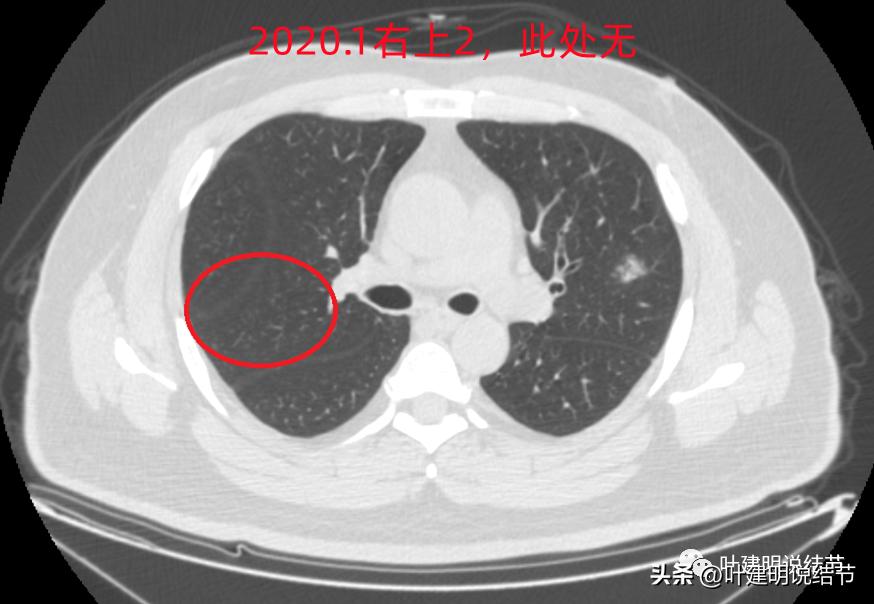

右上病灶2:新出现的,整体轮廓较清,但感觉较散在,不致密,也不是圆形或类圆形,大概是炎性的吧!

2020年时同样位置是没有异常的: